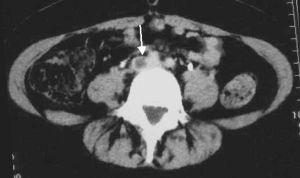

Proximal DVT

Proximal veins are the external iliac, common femoral, greater saphenous, profound (deep) femoral, (superficial) femoral vein, popliteal vein

Consider pharmaco-mechanical (IR) management of proximal DVTs with the following charateristics:

- Objectively diagnosed (i.e., CT or US)

- Ileofemoral DVT that is a candidate for thrombectomy (should have the following):[13]

- Acute iliofemoral DVT (symptom duration <21 days)